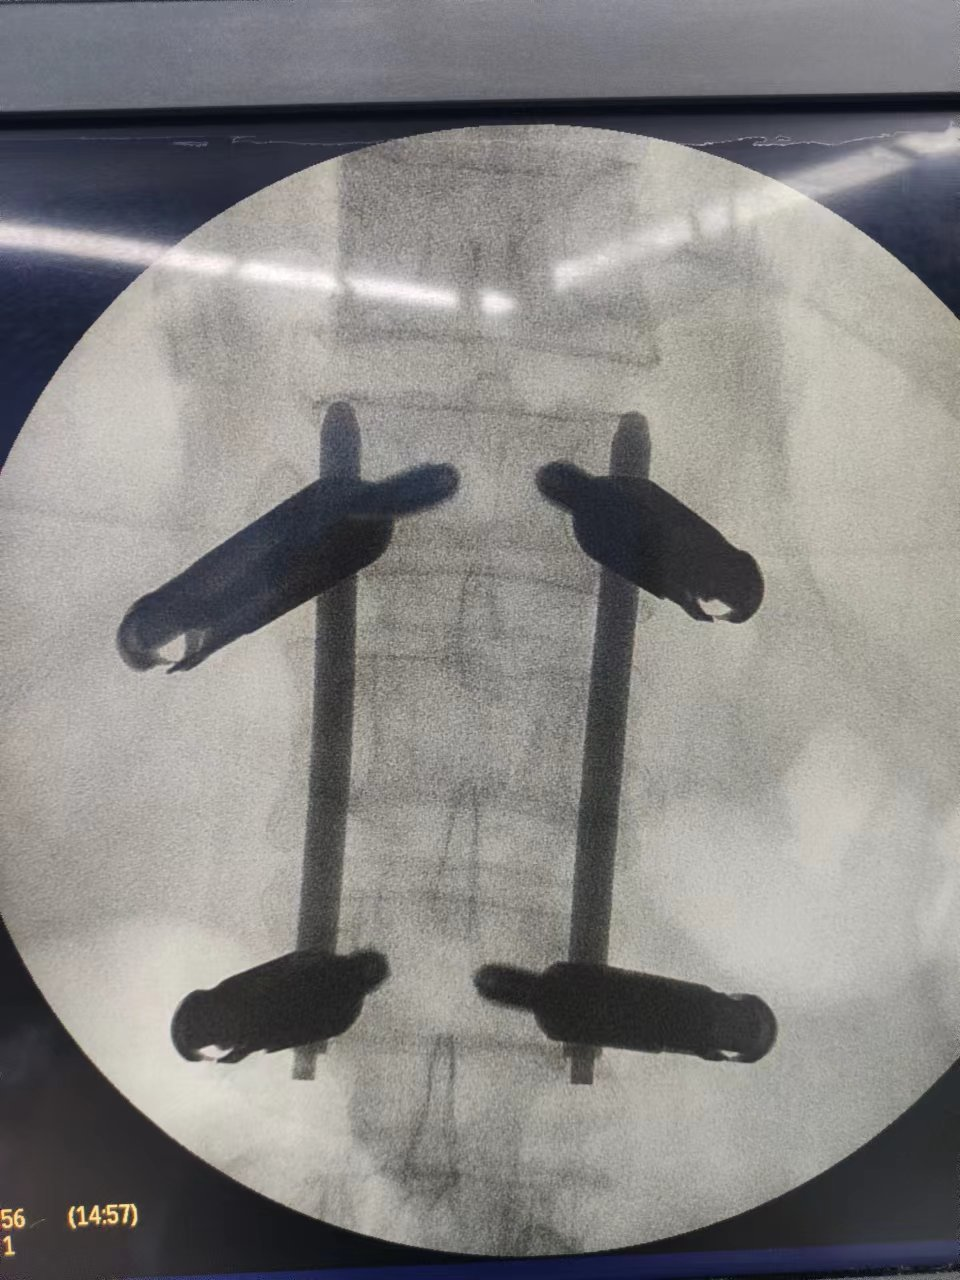

經過充分的術前準備,在麻醉科、手術室等的密切配合,骨科團隊通力合作,手術順利完成,術中4個釘道切口長度僅為1.5cm。

▲透視見椎體高度相高度恢復滿意